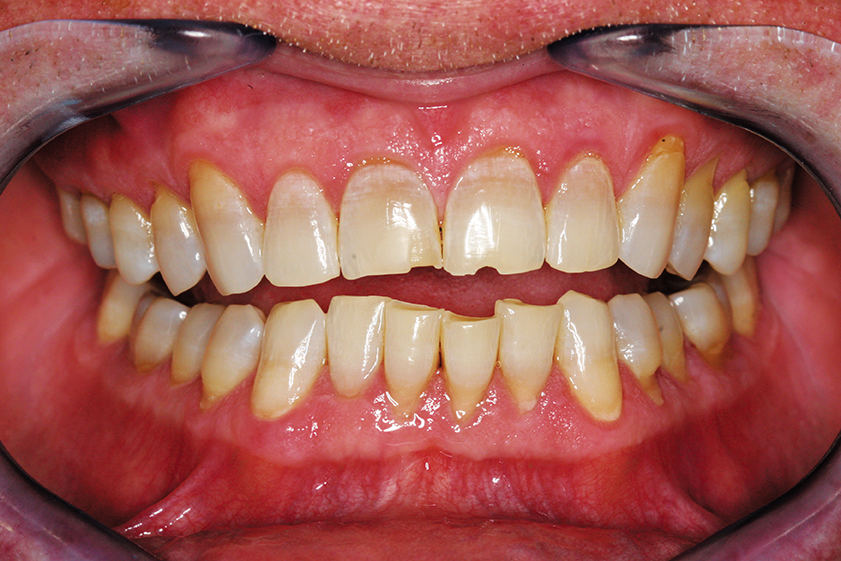

Post-orthodontic care wasn’t rushed to establish solid tooth positions and occlusion. This involves three months of retention along with deprogramming, whitening and equilibration at the end. (Fig. 2).

Repair of chipped and damaged teeth was done additively using an erbium laser, thin, low-depth diamond bevels and placement of BRILLIANT EverGlow® Duo Shade B1/ A1 (Fig. 3).

Fig. 3